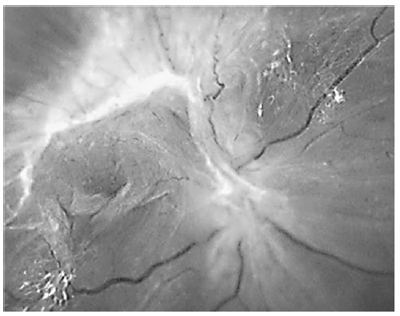

Acerca do descolamento de retina tracional mostrado na figura acima, assinale a alternativa correta.